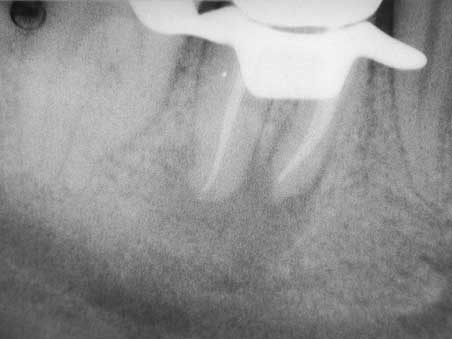

WF – Kontrolle

Veröffentlicht 16. Februar 2009 am 452 × 339 in Apikale Aufhellung (3)